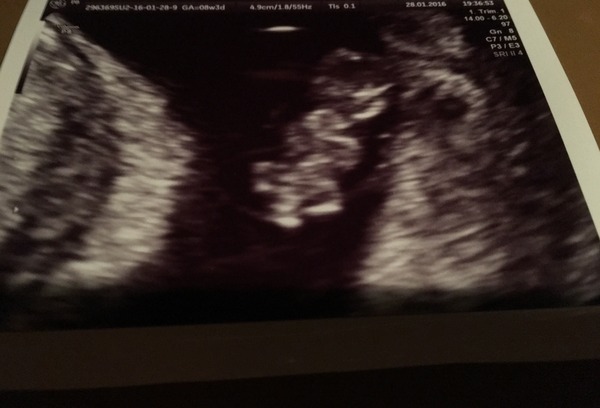

Nevlet · 29/01/2016 06:52

Look who we got to meet last night!

Aww nev what a lovely little bean!

Nev that's a lovely scan! Is that a 12 weeker? Sorry if missed tHat.

Morning shelb no 8+3 yesterday. I had been panicked by lack of symptoms so OH booked it to try and put my mind at rest. Lovely clear pictures but am paranoid heart beat is too fast even though they said it was totally normal!

Nev how amazing is your scan, it's so clear.

Nev~ the scan is great! Did they confirm your dates?

Lovely scan Nev! And 8+3 with a heartbeat Smile Don't worry about it going twice as fast as yours, apparently that is completely normal. It's got a lot of work to do building a human!

Thanks for the nice comments... Was so excited I had to share! I estimate 8+3 from LMP but do have PCOS and bonkers cycles scan put at 8 exactly. So very close. Heart rate was 185 none of my apps go above 180!

Nev I didn't get a heart rate reading at my early scan, I wonder what it was..if the sonographer wasn't concerned then I wouldn't be either.